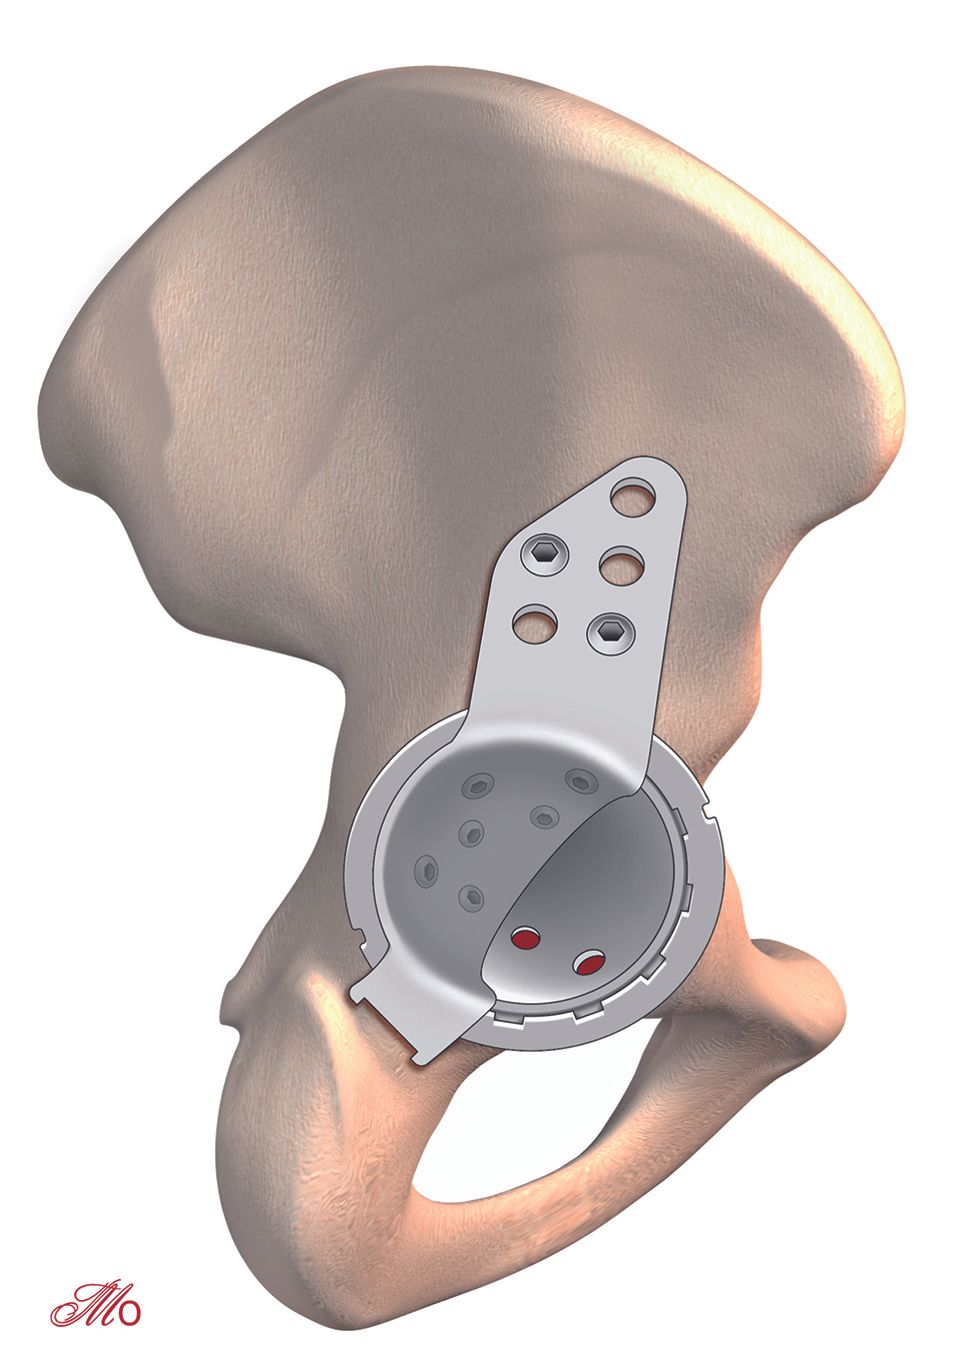

The clinical articles in this issue address several domains of knee and hip surgery. Ligament reconstruction is represented by a practical guide on avoiding tunnel convergence during multiple-ligament knee surgery and a technical review of PCL reconstruction using the INLAY technique. Patellofemoral pathology is examined through technical advice for patellofemoral arthroplasty, while revision hip surgery is addressed through a discussion of the philosophy of total hip replacement revision at Mayo Clinic.